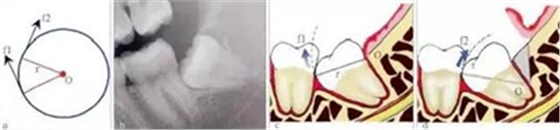

3.3.1 轉(zhuǎn)動(dòng)軸心與圓弧運(yùn)動(dòng)

這一原理在前傾或水平阻生智齒的拔除中運(yùn)用最廣。可以通過改變牙體轉(zhuǎn)動(dòng)脫位時(shí)的運(yùn)動(dòng)軸心,來改變牙體上各點(diǎn)的運(yùn)動(dòng)方向(圖4),從而避開阻力而使牙齒脫位。但在此過程中,牙槽窩的擠壓變形仍不可避免。尤其是舌側(cè)骨板的骨折,更是經(jīng)常發(fā)

生的事件。要進(jìn)一步減少對(duì)牙槽窩的擠壓,則需要對(duì)牙根進(jìn)行進(jìn)一步的切割。

圖4 轉(zhuǎn)動(dòng)軸心與圓弧運(yùn)動(dòng)。在圓周運(yùn)動(dòng)(旋轉(zhuǎn))中,圓周上所有點(diǎn)的運(yùn)動(dòng)方向(f1、f2)均為切線方向,與通過該點(diǎn)的半徑(r)相垂直(圖a)。當(dāng)牙齒發(fā)生旋轉(zhuǎn)脫位時(shí),其阻力點(diǎn)的運(yùn)動(dòng)方向會(huì)隨著轉(zhuǎn)動(dòng)的軸心點(diǎn)的變化而變化,從而避開阻力。前傾

阻生智齒(圖b)脫位時(shí),阻力分析如圖c所示,因阻力點(diǎn)位于旋轉(zhuǎn)中心(O)的下方,旋轉(zhuǎn)脫位時(shí),其阻力點(diǎn)的運(yùn)動(dòng)方向(f1)是向前上的,被鄰牙所阻擋。如果按照?qǐng)Dd所示,去除遠(yuǎn)中骨質(zhì)(灰色部分)或切割牙體(r)后,旋轉(zhuǎn)中心(O)下移,阻

力點(diǎn)的運(yùn)動(dòng)方向就改變?yōu)橄蚝笊希╢2),而得以避開鄰牙阻擋而脫位。